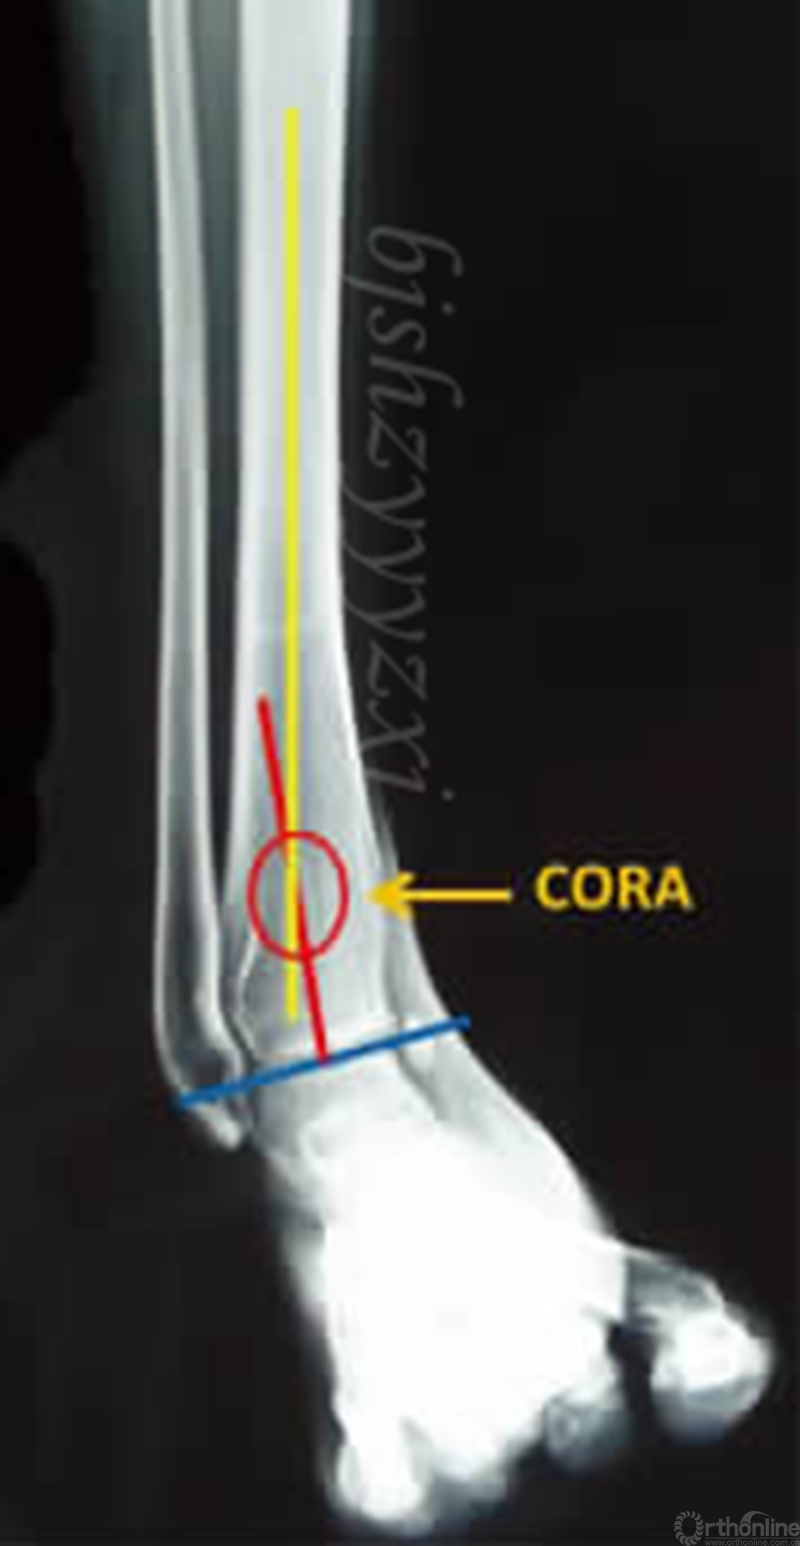

在全长片上画出下肢机械轴,可从整体判断力线,肢体长度,有无合并畸形。根据Paley提出的矫形分析原则,踝关节内翻导致下肢机械轴线内移,胫骨远端外侧角(LDTA)增大,胫骨近端和远端的解剖轴线相交于旋转成角中心(CORA),畸形顶点靠近关节面是此类畸形的特点,CORA的确定为截骨和安装外固定提供了重要参考。(见图2)

图2 在X线片上画出胫骨近端和远端的力线,相交于畸形的旋转成角中心(CORA)